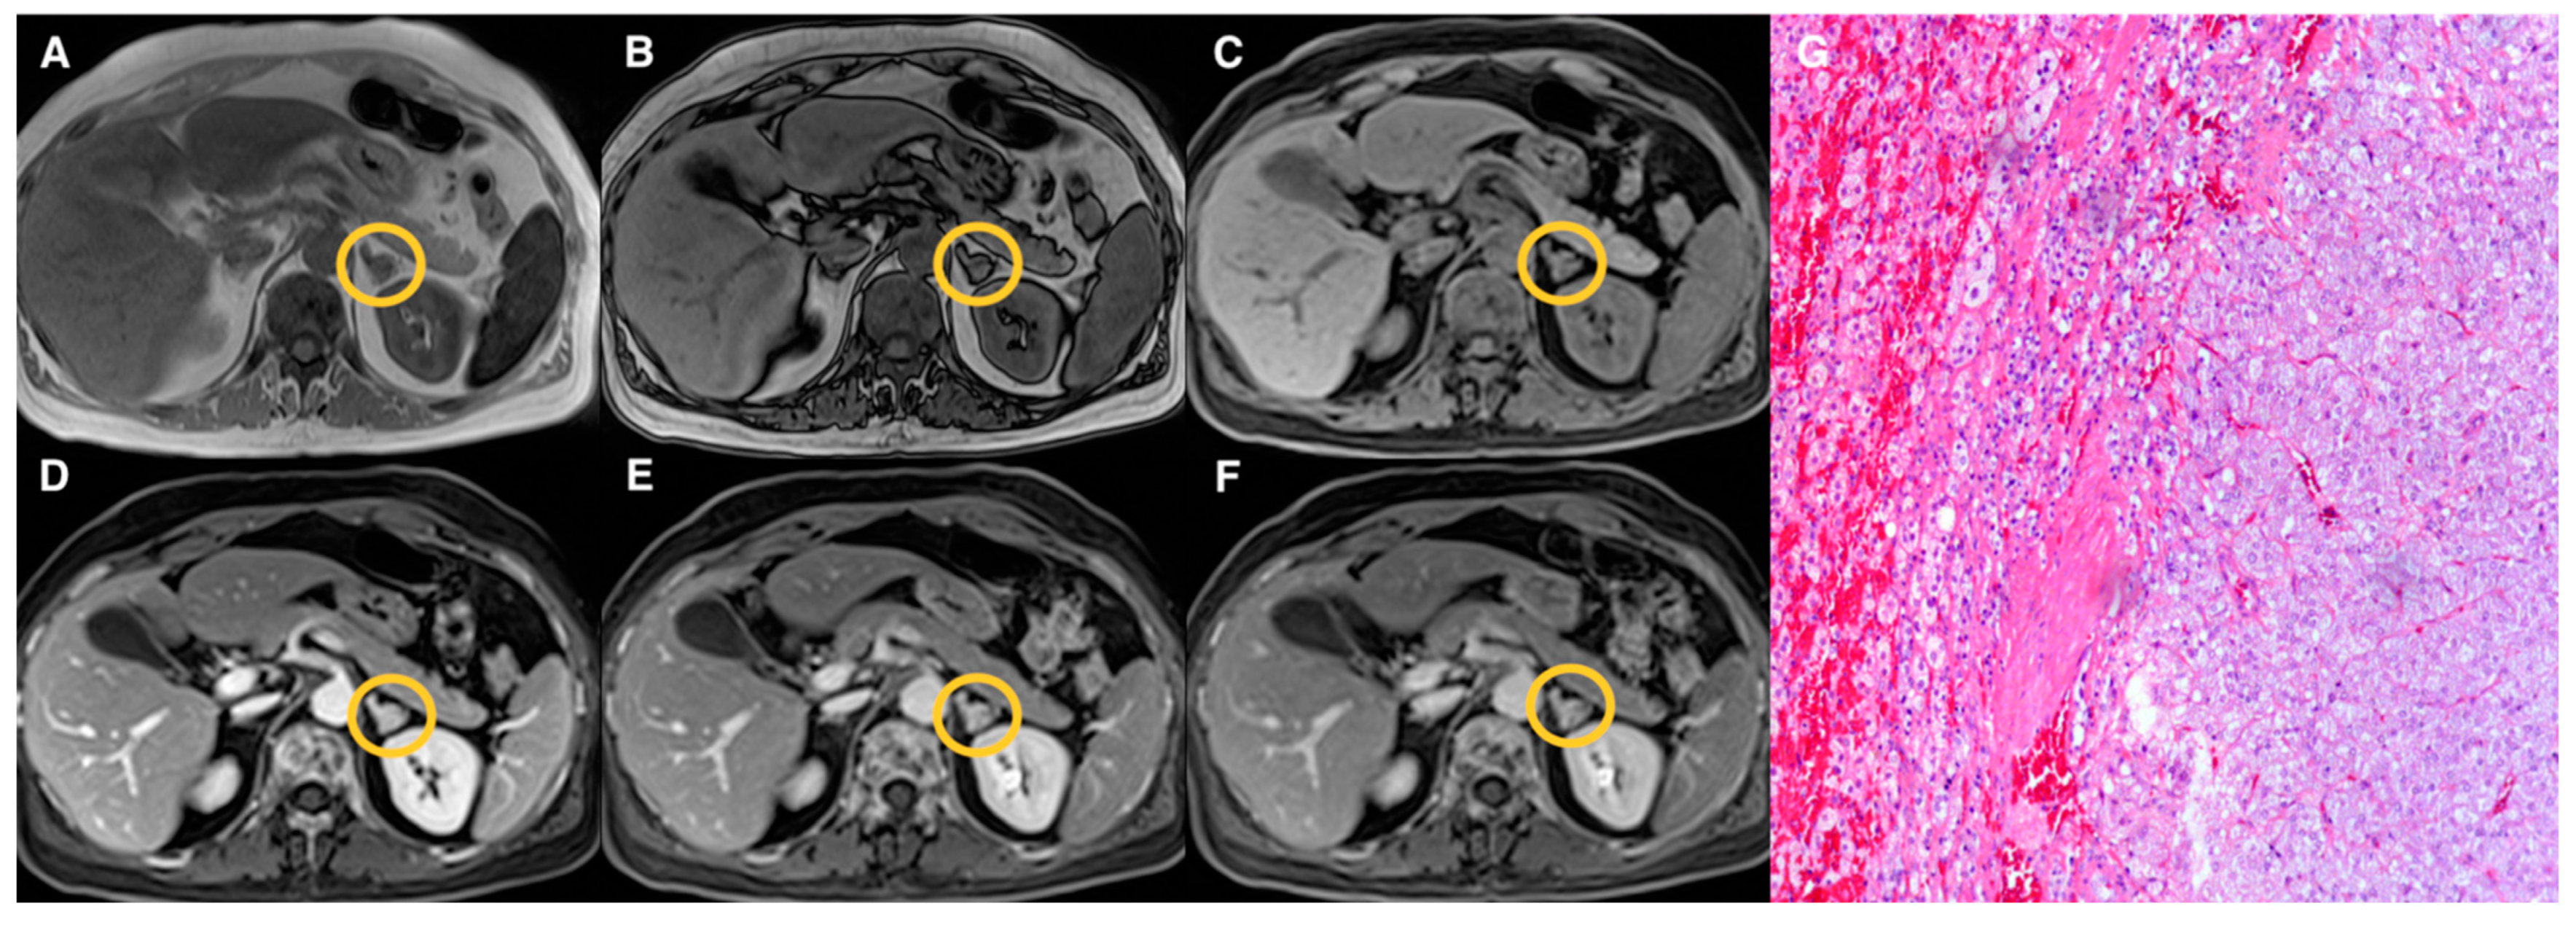

2.3. Image Analysis

3. Results